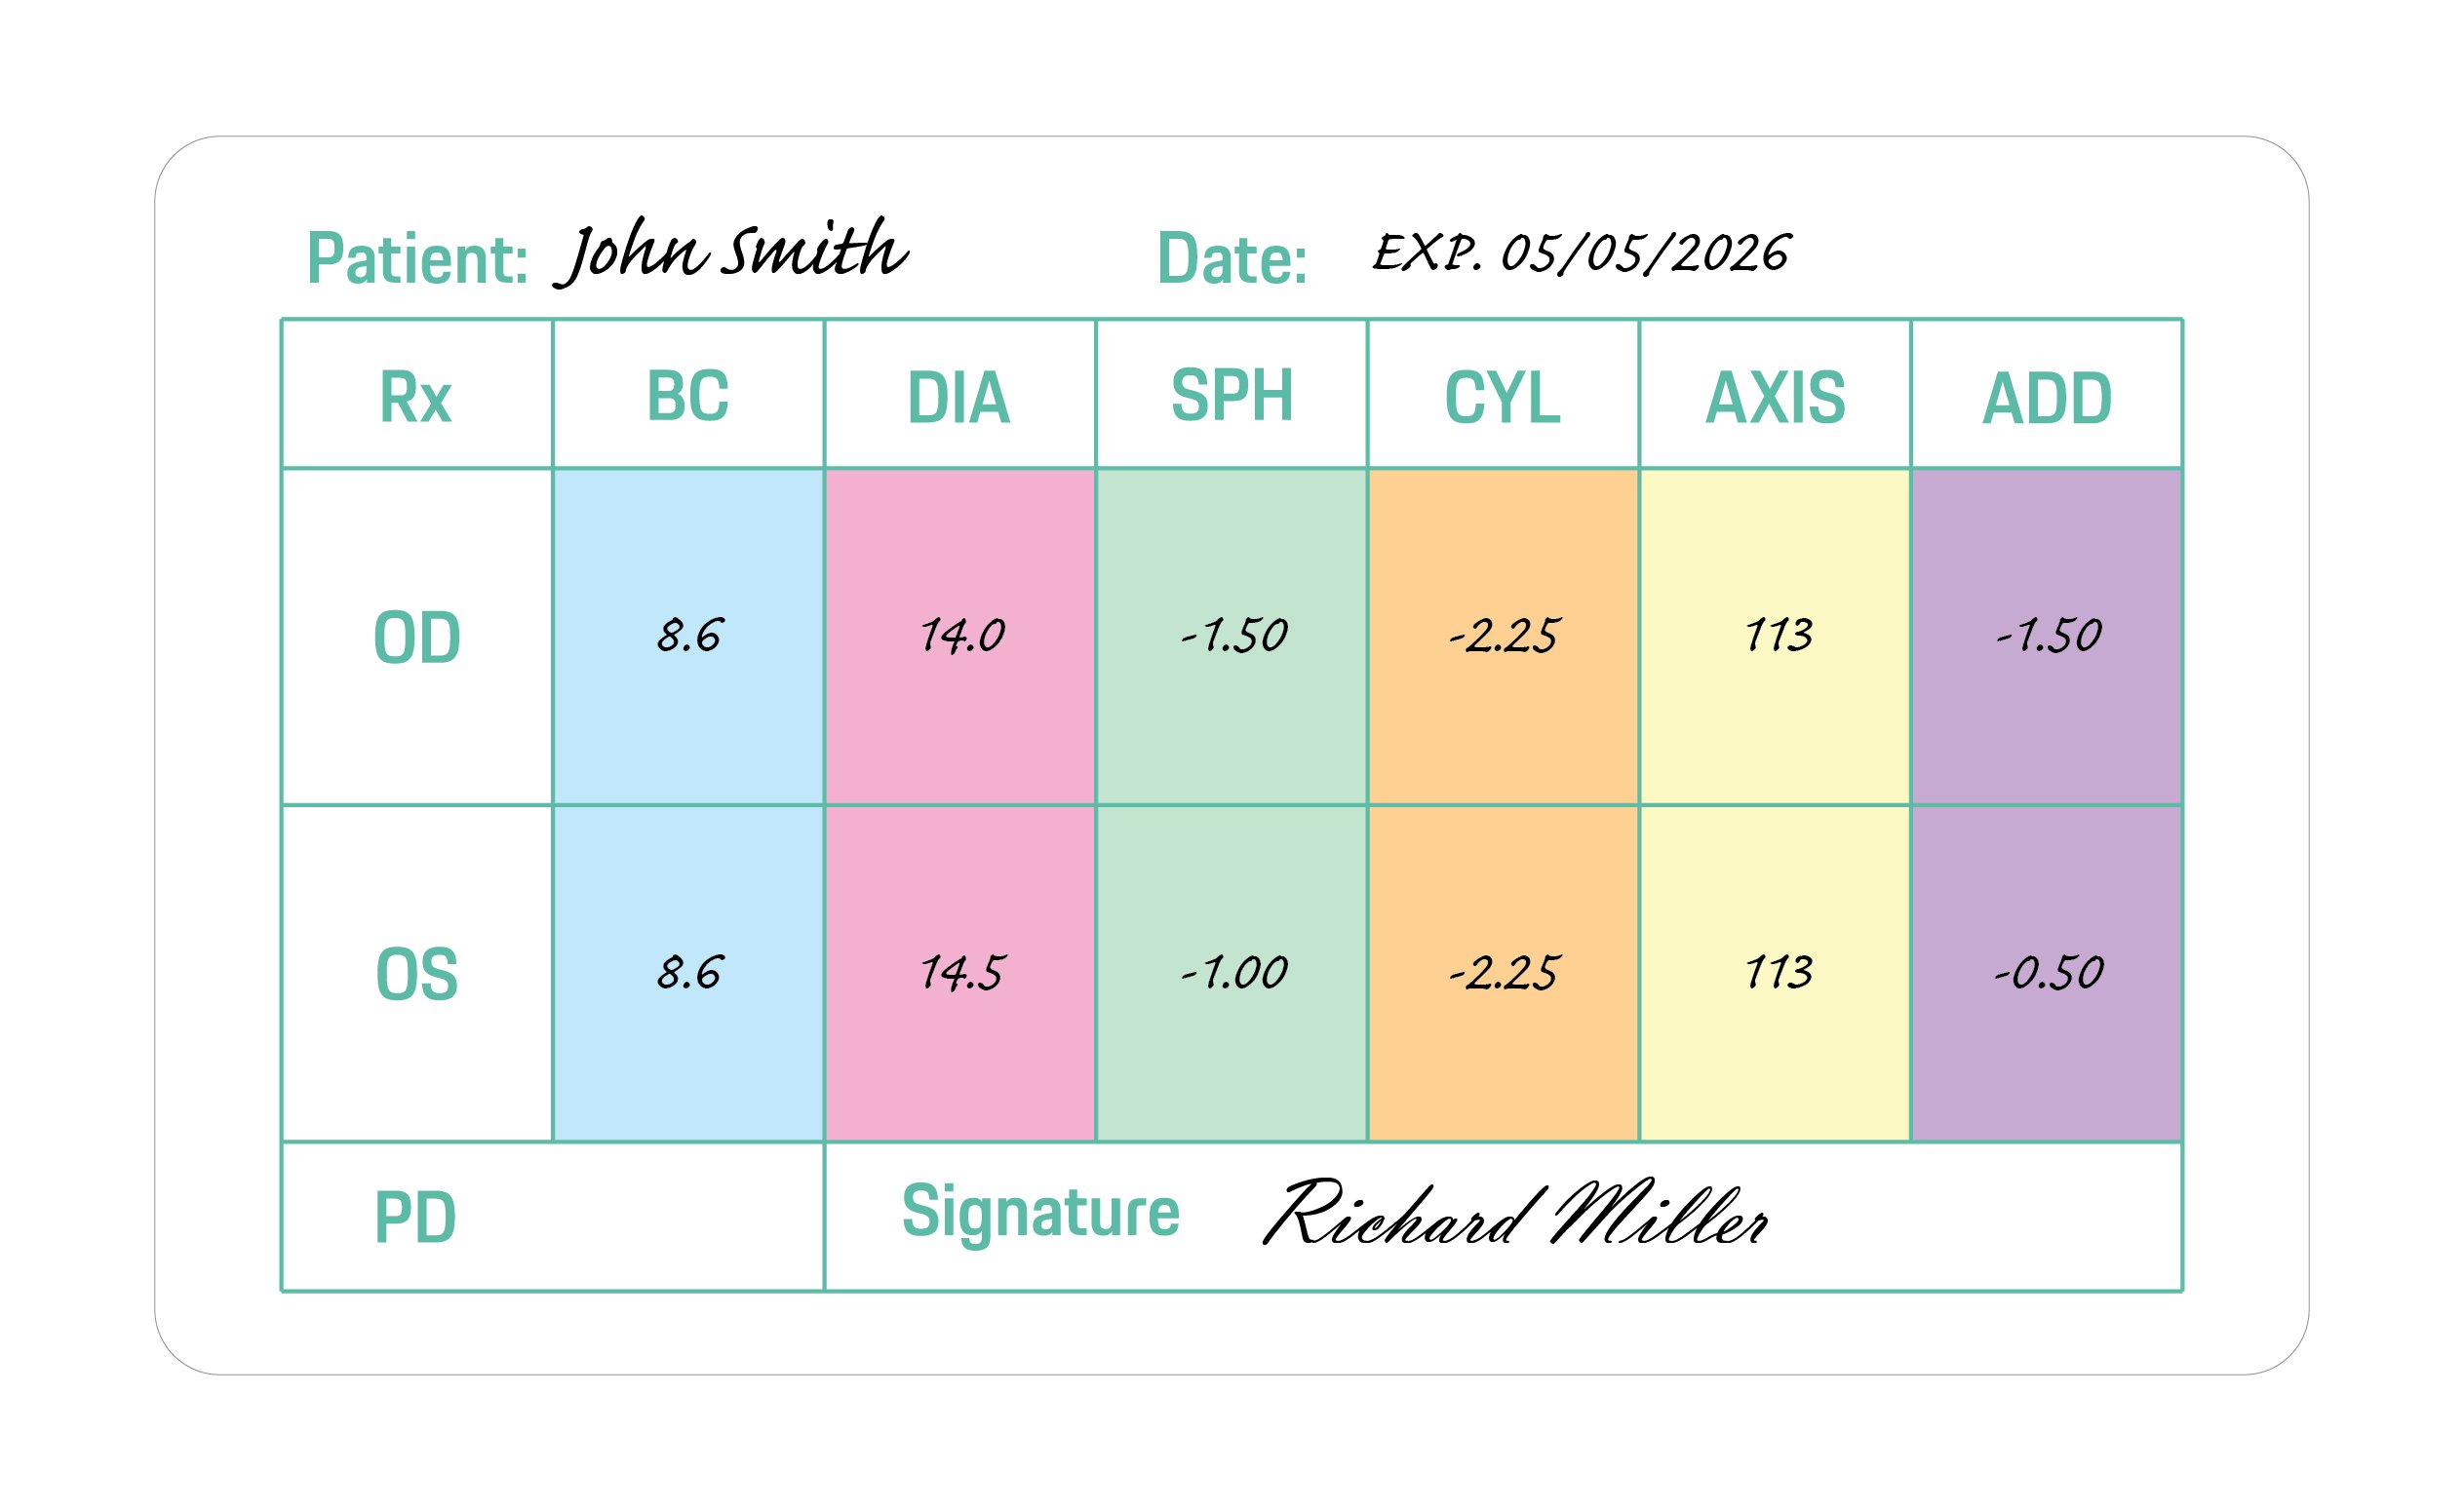

OD is an abbreviation for the Latin term oculus dexter which means right eye. Notice that the right eye information is asked for first even though we typically read from left to right.

OS is an abbreviation of the Latin oculus sinister which means left eye. That will be referenced on the far right column of the prescription.

B.C. is short for base curve measurement indicates the back curvature of your contact lens, in millimetres. This is important for comfort, as the BC of your contact lenses should match your eye's natural curve as closely as possible to ensure a better fit when you are wearing your contact lenses.

DIA is short for "diameter," or the distance from one edge of the contact lens to the other. This is measured in millimeters.

SPH is short for sphere. The sphere of your prescription indicates the power on the lenses that is needed to see clearly. A plus (+) symbol indicates the eyeglass wearer is farsighted. A minus (-) symbol indicates that the eyeglass wearer is nearsighted.

CYL is short for cylinder. The cylinder indicates the lens power necessary to correct astigmatism. If the column has no value (is blank), it indicates that the eyeglass wearer does not have astigmatism. If this is the case on your prescription, you can leave it blank when entering it in.

AXIS is a prescription will include an axis value for those with astigmatism. This number represents the angle of the lens that shouldn't feature a cylinder power to help correct your astigmatism.

ADD is short for "additional correction." This is where details about bifocals, multifocal lenses or progressive lenses would appear.